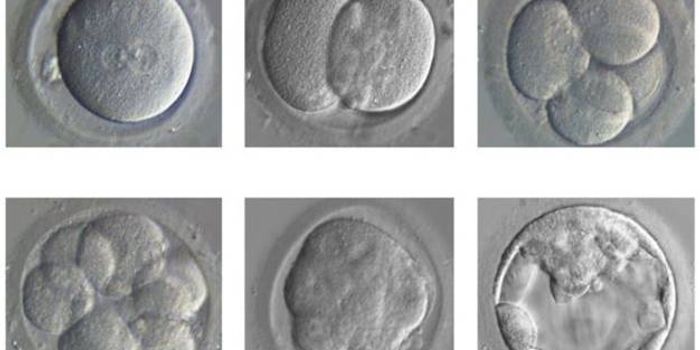

APR 19, 2015Genetics & GenomicsAneuploidy-the incorrect number of chromosomes in a cell-is quite common in early embryos; it's also the primary reason ...

FEB 02, 2016Clinical & Molecular DXIn a historic, unprecedented move, UK national fertility regulators have given the green light for scientists to use the ...